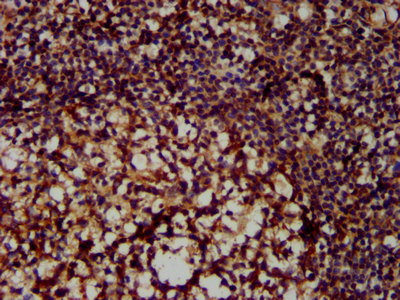

IHC image of CSB-PA015250LA01HU diluted at 1:300 and staining in paraffin-embedded human tonsil tissue performed on a Leica BondTM system. After dewaxing and hydration, antigen retrieval was mediated by high pressure in a citrate buffer (pH 6.0). Section was blocked with 10% normal goat serum 30min at RT. Then primary antibody (1% BSA) was incubated at 4°C overnight. The primary is detected by a biotinylated secondary antibody and visualized using an HRP conjugated SP system.

ApplicationsImmunoFluorescence, ELISA, ImmunoHistoChemistry

- ApplicationsImmunoFluorescence, ELISA, ImmunoHistoChemistry